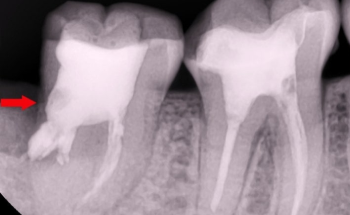

아말감 후 2차충치가 생기는 이유

신경치료후 크라운을 씌워야 하는 이유